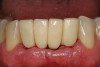

Figure 8  Final ceramo-metal restoration.

Figure 8

The patient was given postoperative instructions and advised to maintain a soft diet for 6 to 8 weeks to protect the implants. The patient was followed weekly for the first 3 weeks and monthly thereafter. After 4 months of healing, the provisional restoration was removed and the soft tissues were examined. Mature, keratinized gingival tissues were present facially, lingually, and interproximally. Nonkeratinized tissue could be seen at the tissue surfaces of the ovate pontics and in the intrasulcular regions of the implant abutment units. No clinical probing depths beyond 1 mm were found adjacent to the abutments. The healed tissue represented an acceptable clinical result especially in light of the gap that had been present at the time of implant placement (Figure 7A and Figure 7B). Final impressions were made, and the permanent ceramo-metal screw-retained prosthesis was placed within 8 weeks (Figure 8).

This patient has been followed for 4 years with no complications and no discernable clinical changes in soft- or hard-tissue levels.